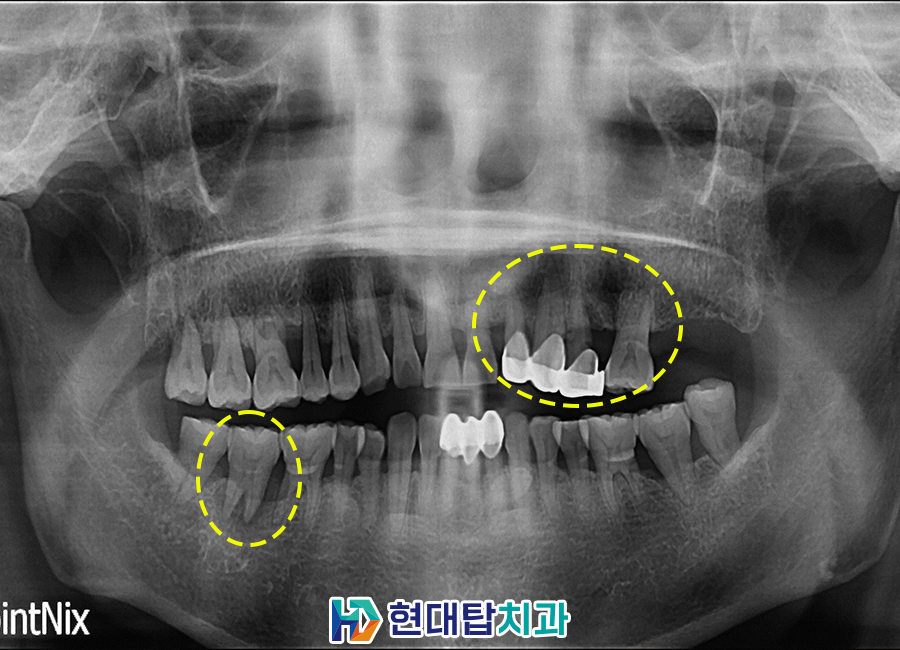

위 환자분께서는 식사하실 때 이가 흔들리는 느낌이 드신다며 치료를 받으러 내원해 주셨는데요. 파노라마 촬영 결과, 왼쪽 위와 오른쪽 아래 어금니 부위에 치아 뿌리 염증으로 잇몸뼈가 많이 녹아 치아가 흔들리는 것으로 판단되어 예후가 좋지 않은 치아를 발치한 후 임플란트 계획을 수립하였습니다.